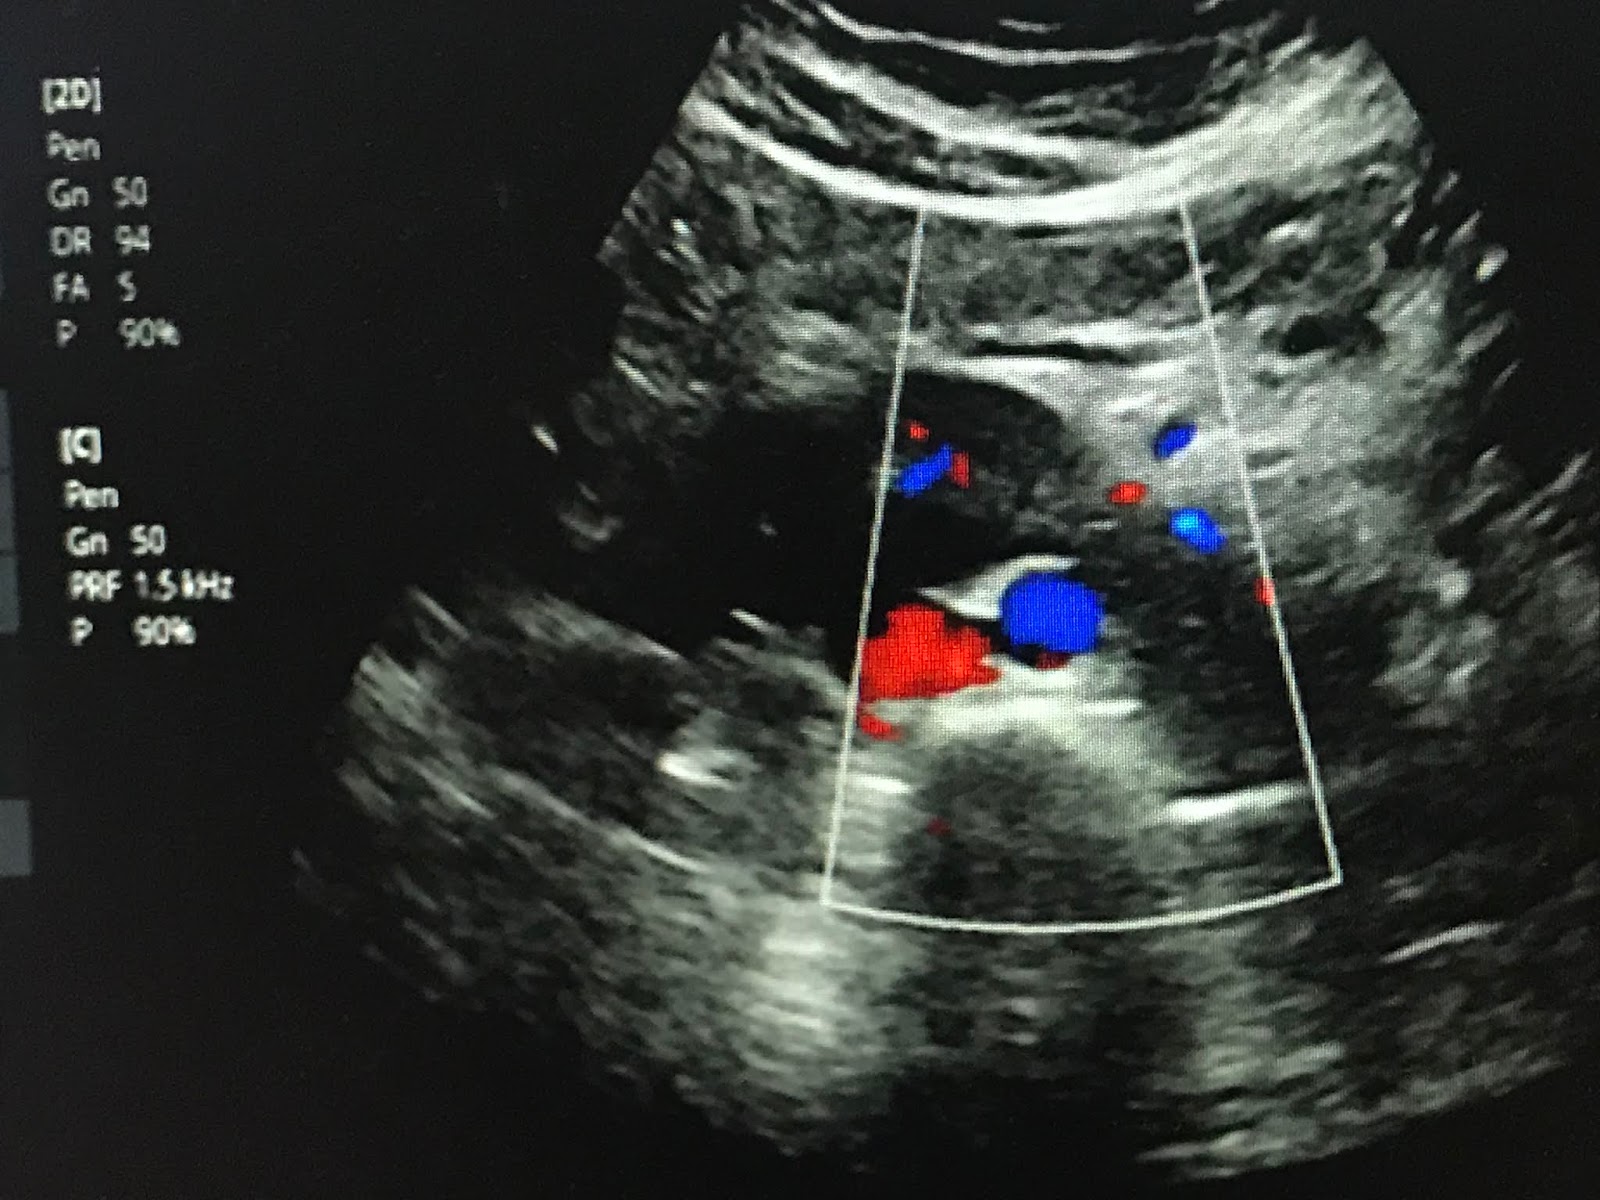

Horseshoe kidney or partial fusion of kidneys ultrasound and color Horseshoe Kidney Images The term horseshoe kidney refers to the appearance of. Horseshoe kidney is the most common renal fusion abnormality characterized by fusion of one pole of each kidney, typically the lower pole. However, it's not just the shape and structure of the kidneys that is abnormal. Horseshoe kidney is probably the most common fusion anomaly. A horseshoe kidney is a congenital. Horseshoe Kidney Images.